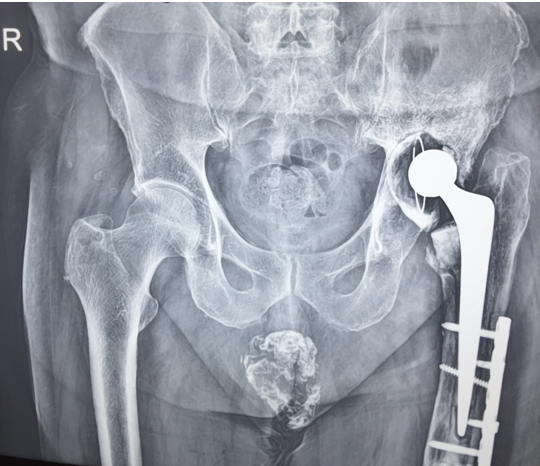

In a series of delayed union with internal fixation over 47 patients regardless of the fracture sites communition or inadequate fixation, had union in all patients including a case of infected nailing of femur. These patients had reported to Dr. S S Jha three to seven months after internal fixation at other centers. None of these patients were willing to submit themselves for further surgical intervention. Teriparatide 20mcg daily through subcutaneous route was started in all patients with adequate supplementation of vitamin D and calcium. Evident radiological bony union was perceptible after three months with clinical improvement in the initial presenting symptoms of the patients and the osseous consolidation was invariably observed radiologically within four to six months. It was only in six patients that Teriparatide was continuously used for one and half years for reasons of general debility, elderly age and osteoporosis. Radiographs of three difficult cases are being displayed from the series.

Case 1([Figure 1], [Figure 2], [Figure 3], [Figure 4], [Figure 5], [Figure 6], [Figure 7], [Figure 8], [Figure 9])

- Case 1([Figure 1], [Figure 2], [Figure 3], [Figure 4], [Figure 5], [Figure 6], [Figure 7], [Figure 8], [Figure 9])